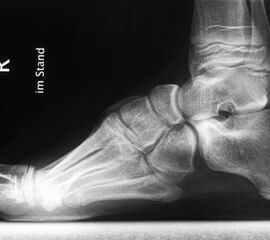

• Fuß belastet dp und seitlich (Abb. 14 und 15)

Typische Merkmale der Standard-Seitaufnahme des Fußes im Stand

• Knöchelgabel ist außen rotiert

• Talus und Calcaneus verlaufen fast parallel

• Sinus tarsi ist einsehbar

• Subtalare Gelenklinie verläuft horizontal und ist breit einsehbar

• Der Abstand Malleolus medialis zum Os naviculare ist verkürzt

• Der Calcaneus erscheint verkürzt

• Der Krümmungsscheitel des Fußes ist erhöht

• Calcaneus pitch ist meist erhöht, der Rückfuß Equinus ist eher selten 12